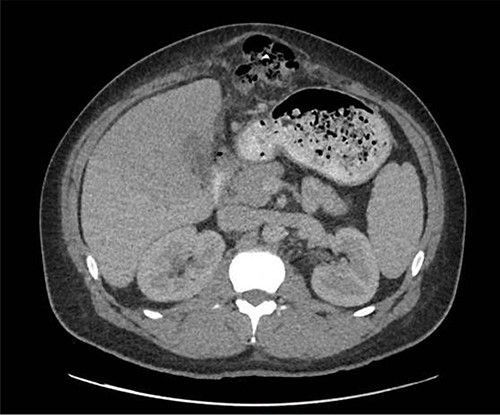

The patient presented after ingestion of an open paperclip and insertion of a sewing needle into his ventral hernia ~4 months prior. He presented with fever, tachycardia and abdominal pain, but a benign abdominal exam, noting only mild tenderness over his large, reducible ventral hernia. A computed tomography (CT) of the abdomen and pelvis showed a 10-cm metallic foreign body extending from the mid transverse colon to the left hepatic lobe with an intrahepatic abscess measuring 9.1 x 7.3 cm (Figs 1–3). In addition, there were two other metallic foreign bodies: one extraluminal in the left upper quadrant, which was stable from prior imaging, and a subcutaneous foreign body above the hernia contents. Blood cultures grew streptococcus intermedius and he was started on broad spectrum antibiotics (piperacillin–tazobactam). The case was discussed with Interventional Radiology (IR) and deemed reasonable for attempt at percutaneous abscess drainage and trans-hepatic foreign body retrieval.

CT view of metallic foreign body within the liver abscess cavity.